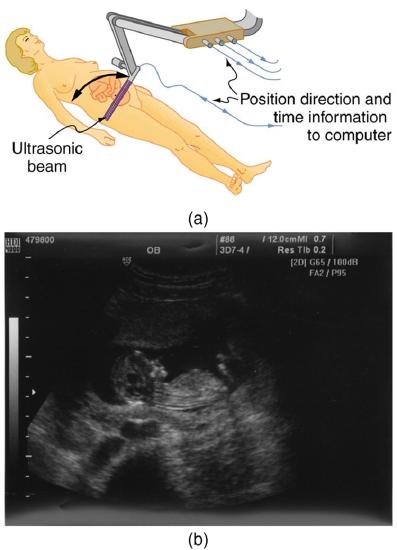

The most common ultrasound applications produce an image like that shown in Figure \(\PageIndex{4}\). The speaker-microphone broadcasts a directional beam, sweeping the beam across the area of interest. This is accomplished by having multiple ultrasound sources in the probe’s head, which are phased to interfere constructively in a given, adjustable direction. Echoes are measured as a function of position as well as depth. A computer constructs an image that reveals the shape and density of internal structures.

How much detail can ultrasound reveal? The image in Figure \(\PageIndex{4}\) is typical of low-cost systems, but that in \(\PageIndex{5}\) shows the remarkable detail possible with more advanced systems, including 3D imaging. Ultrasound today is commonly used in prenatal care. Such imaging can be used to see if the fetus is developing at a normal rate, and help in the determination of serious problems early in the pregnancy. Ultrasound is also in wide use to image the chambers of the heart and the flow of blood within the beating heart, using the Doppler effect (echocardiology).